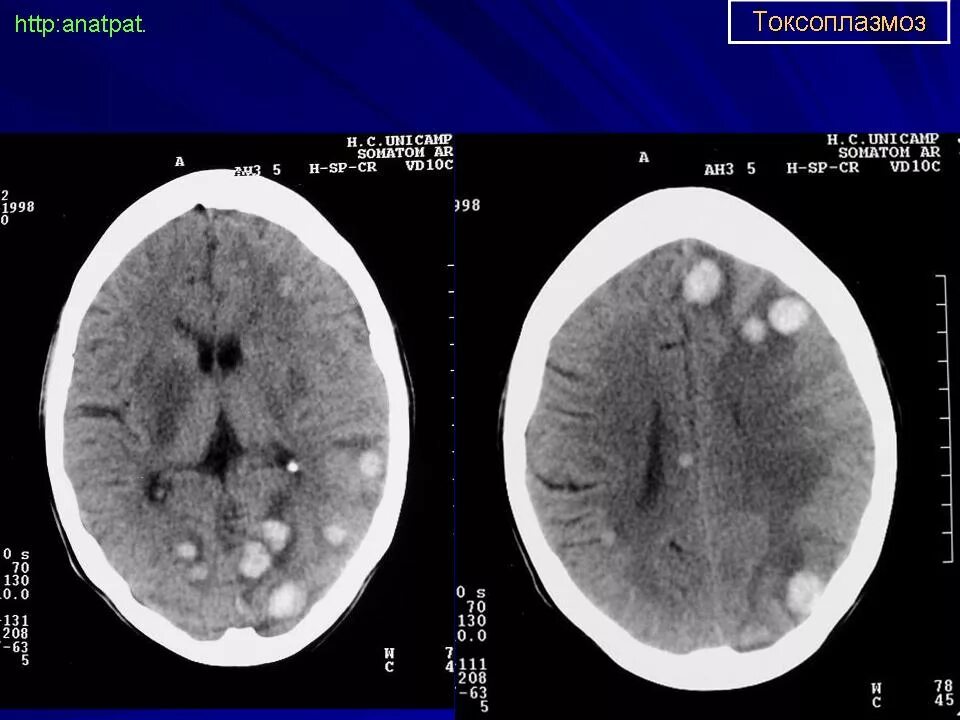

Токсоплазмоз у вич инфицированных